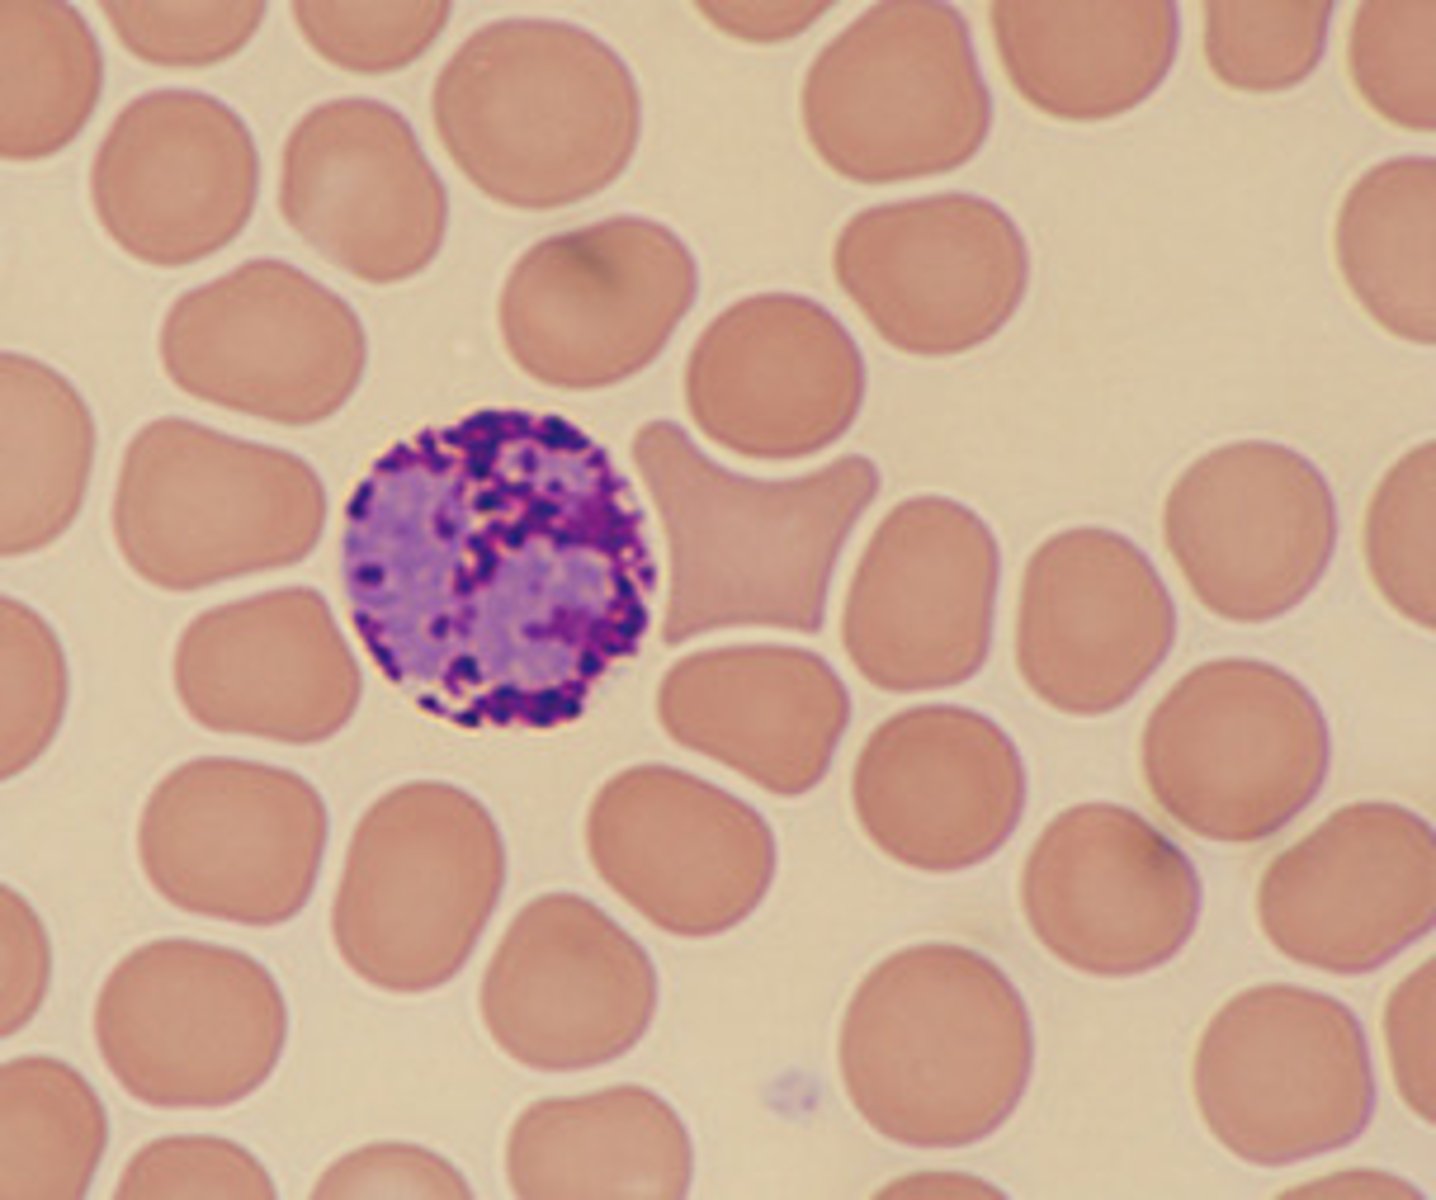

granular lymphocyte

MAMMAL